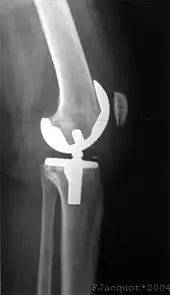

Traitement chirurgical

Dans les années 1970 à 1980, la limite d'âge pour les opérations de reconstruction du LCA se situait environ à 35 ans. Ceci était dû aux possibilités opératoires encore restreintes en raison de la difficulté d'approvisionnement en sang et des mauvaises perspectives de guérison des LC. Aujourd'hui, il n'y a plus de limite d'âge[169]. L'état du genou, les souhaits du patients et sa motivation sont les facteurs essentiels pour la décision d'opérer ou non. Dans la plupart des cas, du point de vue médical, il n'y a pas besoin d'intervention chirurgicale immédiate pour une rupture de LC. Une rupture récente n'est opérée dans l'idéal qu'après six à huit semaines de physiothérapie ou kinésithérapie. Le genou a alors normalement perdu complètement son épanchement articulaire[170]. Dans de nombreux cas, l'opération a lieu plusieurs mois, voire années après la rupture du LC. Par exemple, on la pratique quand une instabilité du genou d'abord faible conduit à des douleurs pour le patient[170]. Dans les pays scandinaves, Norvège, Danemark et Suède, les temps moyens entre la rupture et l'opération sont respectivement de 7, 9 et 10 mois[171], par contre aux États-Unis c'est 2,4 mois. Les quartiles sont de 1,2 et 7,2 mois aux États-Unis, et de 4,2 et 17,8 mois en Norvège[172].

Reconstruction du ligament croisé

La majorité des techniques actuellement utilisées prévoient la reconstruction du LC déchiré, ou ligamentoplastie selon Franke-Clancy. Cette technique classique s’appelle à tort en France le "Kenneth-Jones ou K.J", auteur qui n'a jamais décrit cette technique décrite par Franke en Allemagne (1970), puis popularisée aux États-Unis à très grande échelle par Clancy en 1982. Les restes du ligament rompu sont éliminés et remplacés par un nouveau ligament. Ce nouveau ligament peut être du tissu du patient lui-même (autogreffe du grec αὐτὸς, autos = soi-même), du tissu d'un cadavre (allogreffe du grec ἀλλὸς, allos = autre) ou d'une autre espèce (xénogreffe du grec ξενὸς, xénos = étranger)[208].